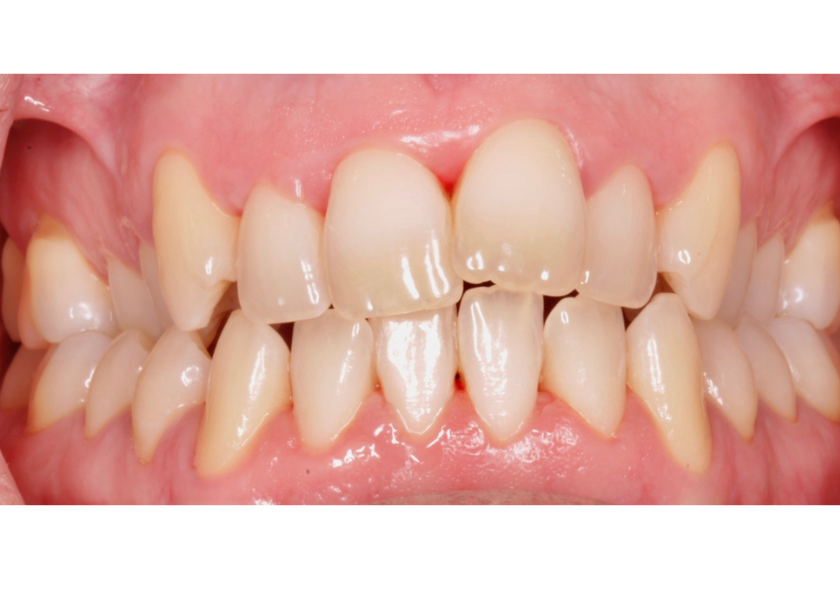

Este paciente acudió a Clínica Dental Urumea para mejorar la estética de su sonrisa. Primero se realizó un tratamiento de ortodoncia con alineadores transparentes Invisalign, para alinear y corregir la mordida cruzada.